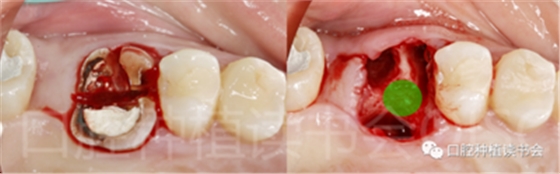

(5)可以有效的關閉拔牙創(chuàng)(圖2、圖3)。

圖2 初期穩(wěn)定性良好的位點,采用愈合基臺+縫合固定的方法關閉拔牙創(chuàng),術后1周獲得良好的軟組織愈合。

圖3 初期穩(wěn)定性不足的位點,采用膠原蛋白覆蓋(倍菱)+縫合固定的方法關閉拔牙創(chuàng),術后10天獲得良好的軟組織愈合。